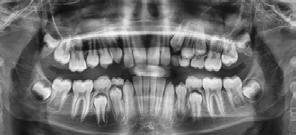

incisivo inferior proinclinado (Figura 7). La radiografía panorámica de inicio muestra 28 piezas dentales con terceros molares en formación con presencia del canino superior derecho impactado (Figura 8).

Figura 6. Oclusal superior e inferior. Figura 7. Radiografía lateral de cráneo. Figura 8. Radiografía panorámica inicio.